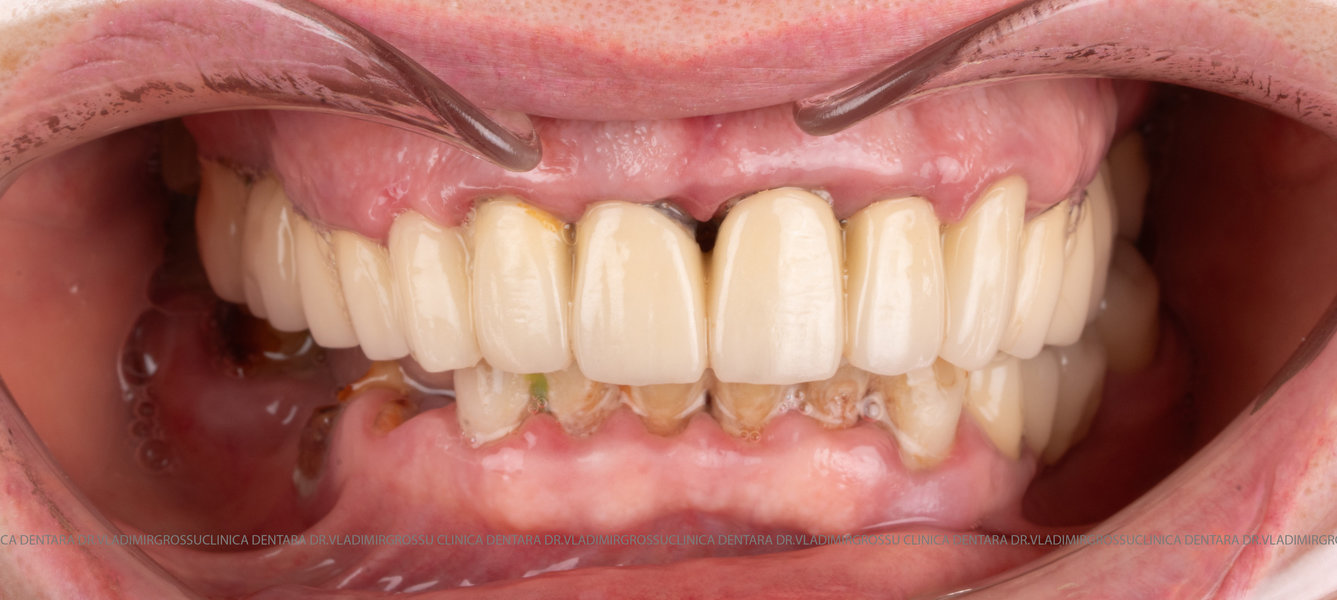

Această metodă este indicată pacienților cu edentație totală sau cu lipsuri dentare multiple, când dinții rămași nu mai pot susține o proteză fixă eficientă. Procedura se desfășoară în două etape:

- Prima etapă constă în inserarea implanturilor și fixarea unei proteze provizorii, realizate de obicei din masă plastică frezată, ce este montată în a doua sau a treia zi postoperator. Suturile sunt îndepărtate după 5-7 zile.

Caz 1

Caz 2